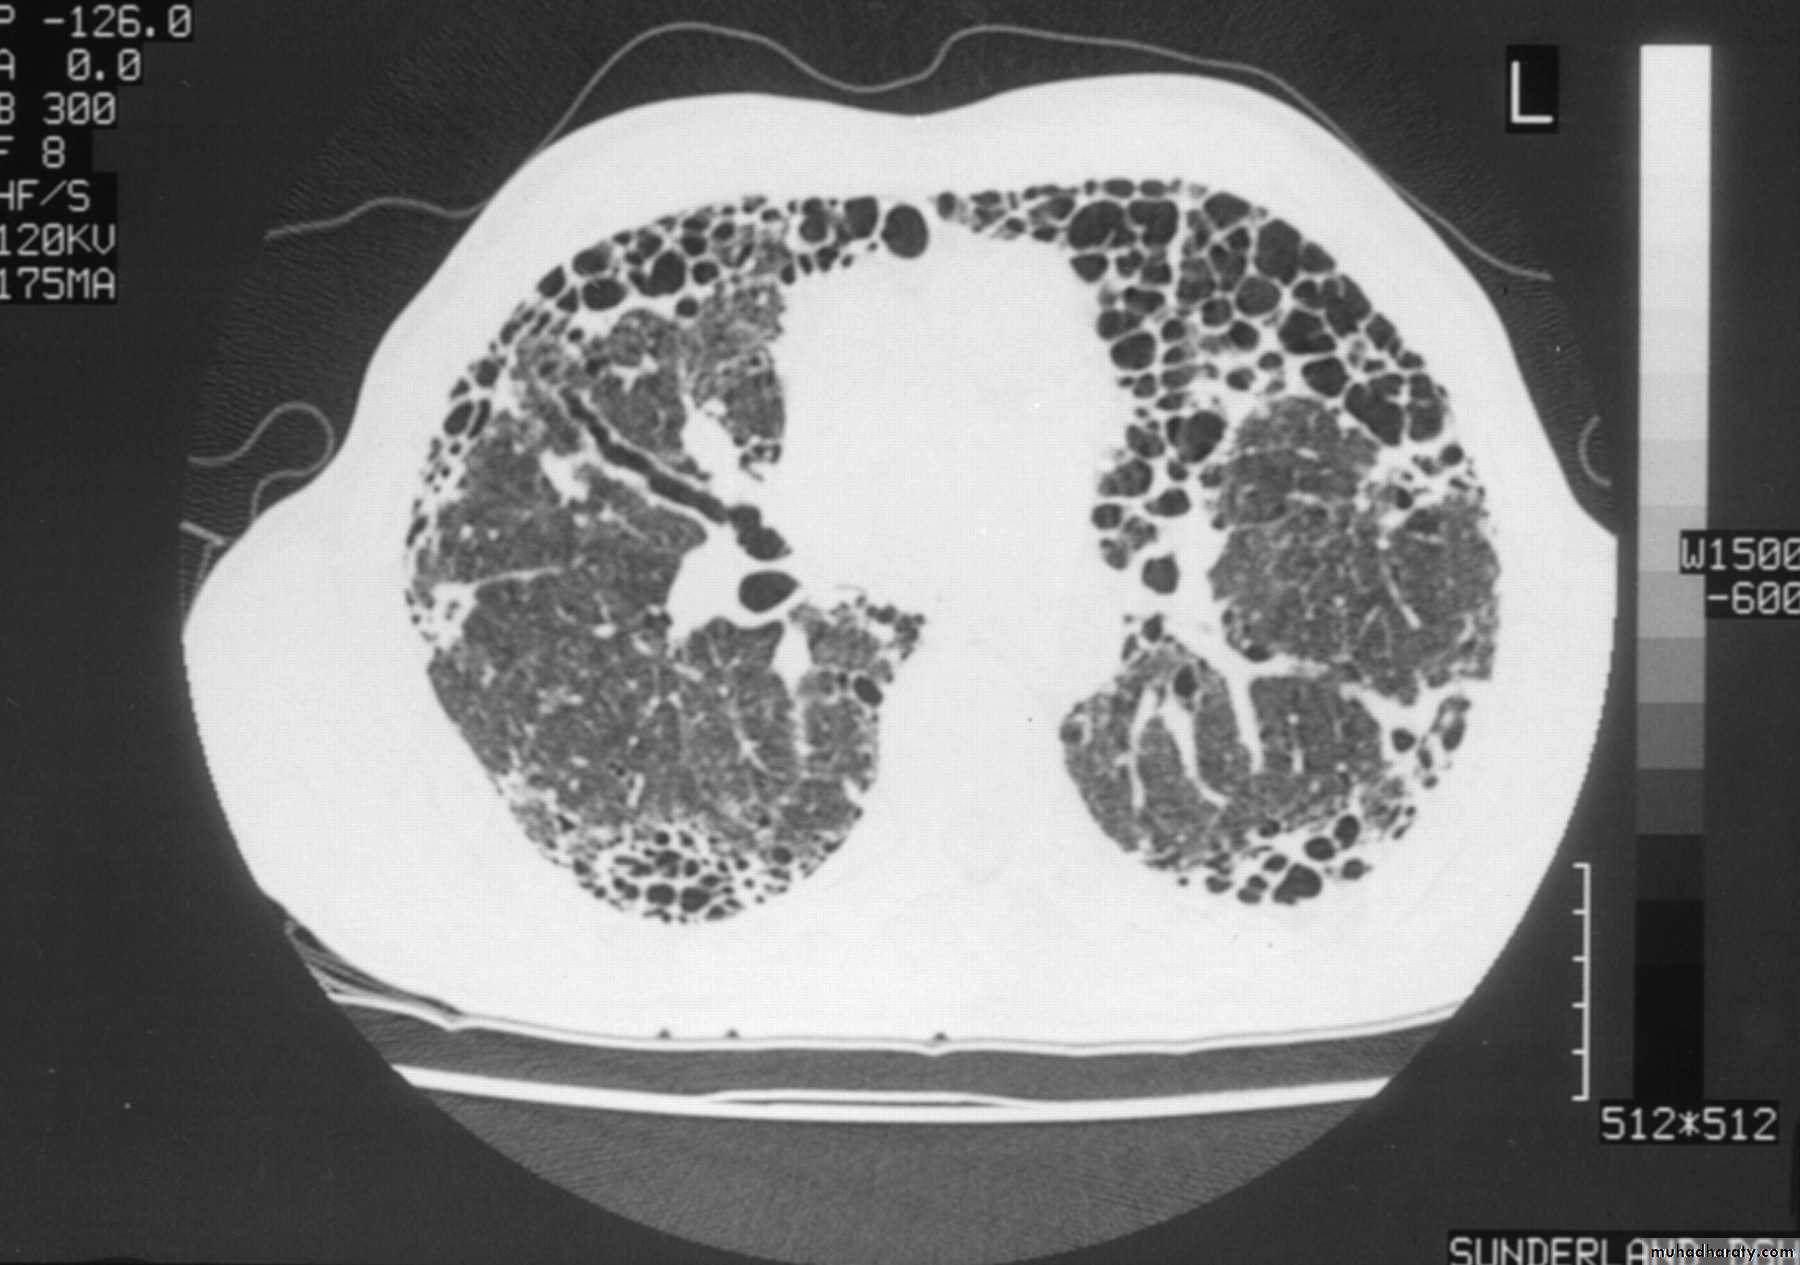

Фиброз легких при раке молочной железы - фото презентация